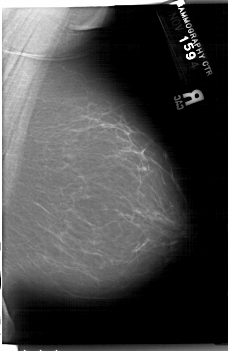

A_1202_1.LEFT_MLO

LEFT_MLO LINES 6511 PIXELS_PER_LINE 4471 BITS_PER_PIXEL 12 RESOLUTION 43.5 OVERLAY